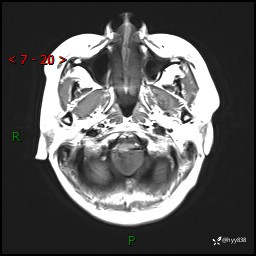

性别:女

年龄:47岁

简要病史:头晕1年余,间断恶心不伴呕吐

颅脑MRI平扫+DWI